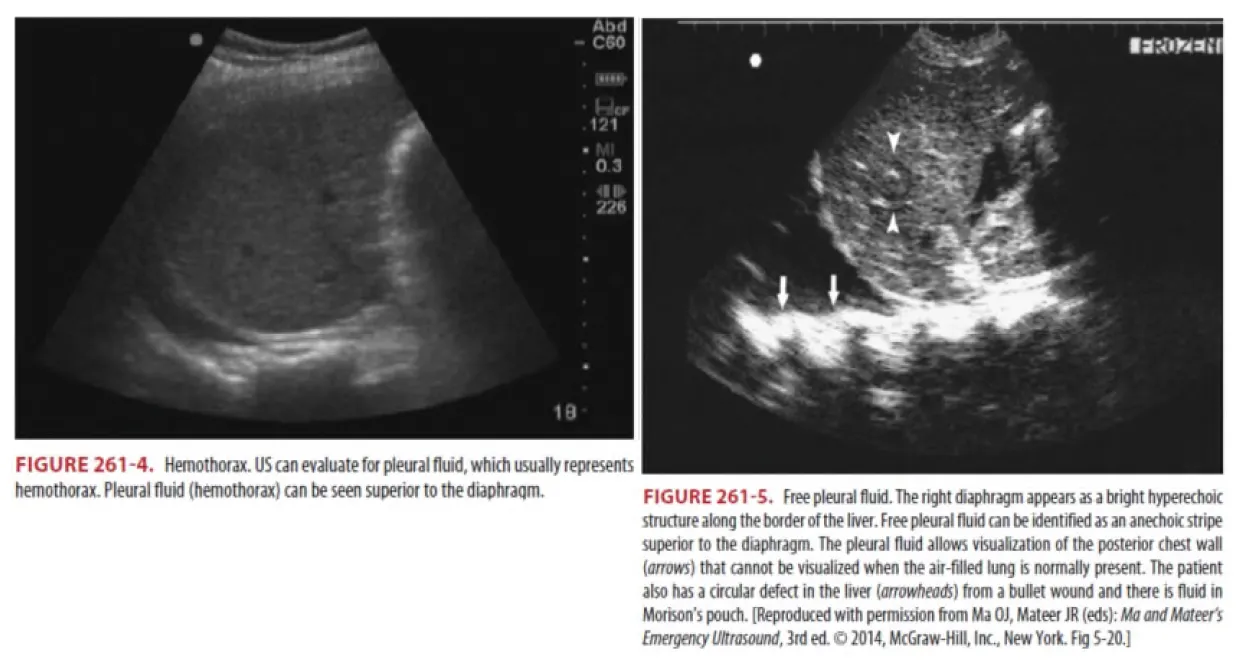

(1) 진단

•

200~300mL 이상 있을 시 upright X-ray에서 주로 관찰되나 supine 자세에서 촬영 시

1000mL 이상의 혈흉도 놓칠 수 있다.

CT : 진단 sensitivity와 specificity가 가장 높다.